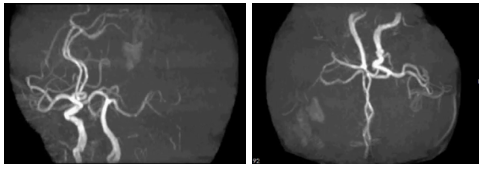

影像诊断

病历夹什么径技·第151期|串联营病历夹:京广连营_https://www.jmylbn.com_新闻资讯_第22张

病历夹什么径技·第151期|串联营病历夹:京广连营_https://www.jmylbn.com_新闻资讯_第23张

病历夹什么径技·第151期|串联营病历夹:京广连营_https://www.jmylbn.com_新闻资讯_第24张

病历夹什么径技·第151期|串联营病历夹:京广连营_https://www.jmylbn.com_新闻资讯_第25张

<<滑动查看下一张图片>>

结论:左侧大脑半球多发梗死灶,T2 flair高信号区域小,左侧颈内-大脑中闭塞,T1 flair提示小出血灶后通过CT排除出血,初步确认为梗死/坏死。